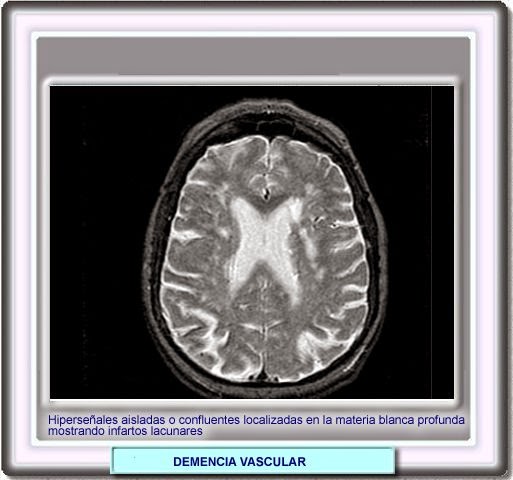

La enfermedad de Binswanger, también llamada encefalopatía subcortical o demencia vascular subcortical, es un tipo de demencia poco habitual que se caracteriza por la afectación de los pequeños vasos sanguíneos situados en la región subcortical del cerebro (demencia vascular)[1] y la aparición en las pruebas de imagen como la resonancia magnética nuclear de rarefacción de la sustancia blanca (leucoaraiosis) y múltiples infartos lacunares subcorticales.[2][3] Los primeros síntomas suelen aparecer entre los 54 y 64 años y consisten generalmente en deterioro cognitivo, más adelante es habitual que se produzca accidente cerebrovascular.[4][5]